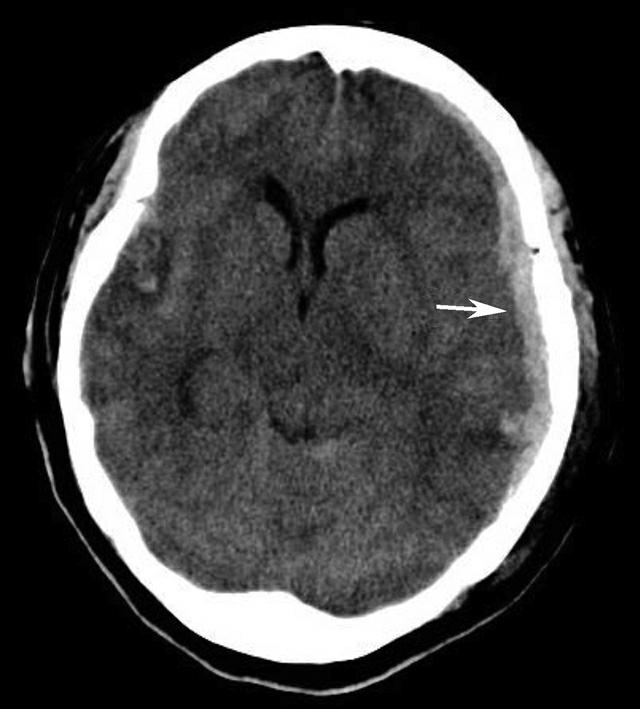

鞍上池是该层面需要重点观察的部位。其形态及密度的改变均提示病变(图1-2-18、图1-2-19),例如鞍上池失去正常五角星或六角星形态、甚至闭塞,或者鞍上池密度升高或不均匀。此外,环池闭塞多见于颅内压严重增高的患者,为诊断脑疝的影像学依据(图1-2-20)。

图1-2-20 环池闭塞

右侧颞叶脑内大血肿(★),产生严重的占位效应,环池受压闭塞(箭),脑疝形成